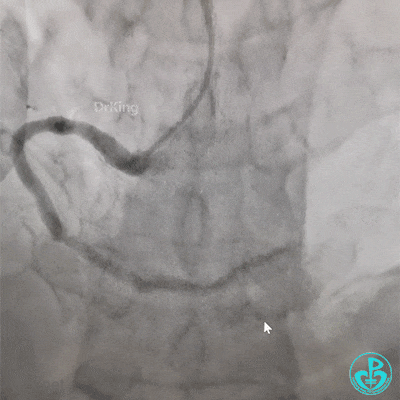

走左边,终于到位,造影。

左边EBU。